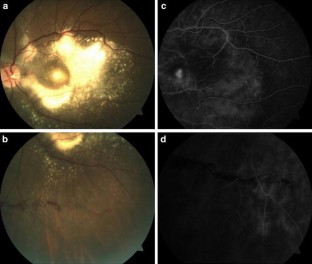

To evaluate the role of intravitreal bevacizumab in the treatment of Coats’ disease diagnosed in adulthood. Prospective, interventional case series. Three patients with Coats’ disease diagnosed in adulthood were managed with a single intravitreal injection of bevacizumab (1.25 mg) with peripheral laser photocoagulation 3 weeks later. All three patients had exudation at the macula (Stage 2B) along with peripheral retinal telangiectasia and aneurysms. They were followed up for 9 months. An appreciable reduction in the exudation at the macula and macular edema was observed in all cases following intravitreal bevacizumab therapy. In all patients, the visual acuity improved, and no signs of recurrence were observed at the final follow-up at 9 months. Intravitreal bevacizumab injections may be effective as an adjunctive treatment for adult-onset Coats’ disease with foveal exudation along with laser photocoagulation to the peripheral retinal vascular abnormalities. Intravitreal bevacizumab was well tolerated by our patients, and no adverse effects were observed.

Fig. 1